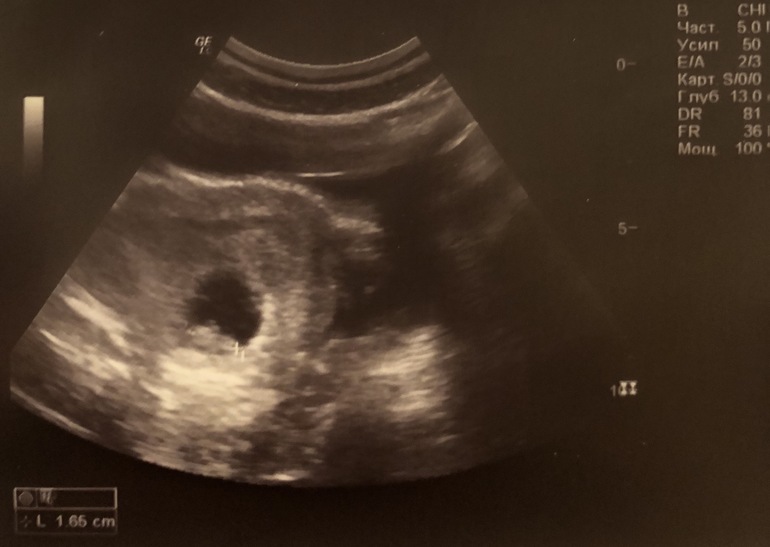

Сегодня 8 ровно. Наконец я побывала на УЗИ, где мне показали малютку и дали послушать сердечко 😍 На сегодня он 1,65 см, ЧСС 162. По узи поставили срок 8+2. Растёт мой хороший 😊

Из плохого - небольшая гематома. Врач сказал лежать. Вот прям совсем лежать, чтоб даже еду муж в постель приносил 🤷🏻♀️ Ну я так не смогу, это же привет депрессия. Уверена, что все будет хорошо и без режима спящей красавицы)